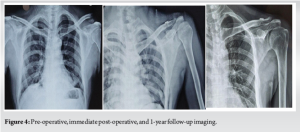

Radiological outcomes

All fractures achieved union by the 6-month follow-up except one, which developed an asymptomatic fibrous union. Radiographs showed evidence of bridging callus in 95% of cases by 3 months. At the 12-month follow-up, there was no loss of reduction or implant failure observed. Residual displacement at the union was minimal, with a mean of 1.1 mm (range 0–2.5 mm) (Graph 1 and Fig. 4). Early post-operative complications were minimal: One patient (5%) experienced superficial wound infection, which resolved with oral antibiotics. One patient (5%) developed mild shoulder stiffness, characterized by a 15° loss of external rotation, which resolved after 8 weeks of physiotherapy. No late complications, such as implant failure, refracture, or coracoid stress fractures, were observed. There was no incidence of symptomatic hardware irritation, and no patient required secondary surgery for implant removal (Table 3).